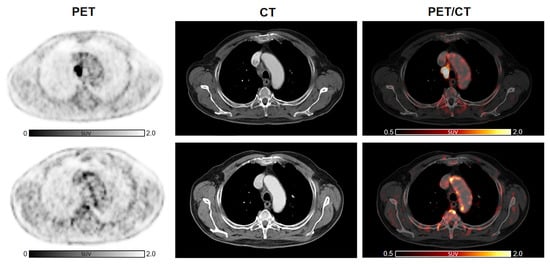

Figure 3. 2-[18F]FDG arterial metabolic activity after ICI therapy compared to baseline in patients previously treated with other anti-cancer therapies. No significant increase in arterial 2-[18F]FDG uptake after immunotherapy can be detected in a subject already treated with RT (A) as well as in a patient who earlier underwent CHT and RT (B). Abbreviations: CHT, chemotherapy; 2-[18F]FDG, 2-[18F]fluoro-d-glucose; ICI, immune checkpoint inhibitors; RT, radiotherapy.

Subsequently, we analyzed the change in arterial inflammatory activity by dividing the patients into two groups, according to the presence of previous anti-cancer treatments, such as CHT or RT, and with presence/absence of CVD risk factors. Cancer immunotherapy with ICI resulted in a significant increase in inflammatory activity in patients without previous CHT (n = 19, TBRCHT(−)_pre = 1.64 ± 0.26 vs. TBRCHT(−)_post = 1.91 ± 0.36; p < 0.001). In patients treated previously with CHT, TBRs remained substantially unchanged (n = 28, TBRCHT(+)_pre = 1.79 ± 0.25 vs. TBRCHT(+)_post = 1.88 ± 0.34; p = 0.18) (Figure 2B). Furthermore, significantly elevated TBR values were recorded after therapy in the subjects without previous RT (n = 25, TBRRT(−)_pre = 1.68 ± 0.25 vs. TBRRT(-)_post = 1.93 ± 0.38; p < 0.001), while no significant changes were observed in patients with prior RT (n = 22, TBRRT(+) _pre = 1.78 ± 0.26 vs. TBRRT(+)_post = 1.84 ± 0.29; p = 0.34) (Figure 2B). Representative images are shown in Figure 3 as well as in Figure 4.